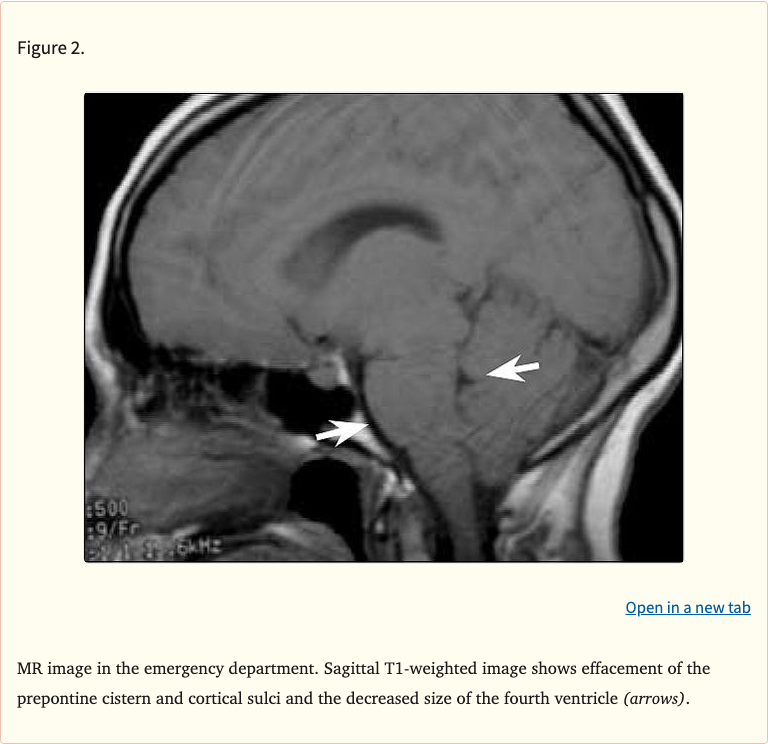

Figures